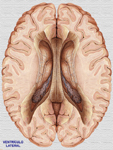

Ventrículo lateral